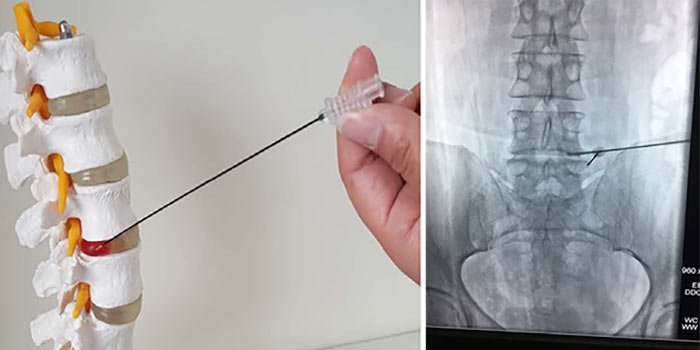

Диагноз подтверждается биопсией. Врач получает фрагмент опухолевой ткани и отправляет его в лабораторию для цитологического и гистологического исследования, а также молекулярно-генетических анализов. Материал для биопсии может быть получен различными способами:

- Чаще всего проводят пункционную чрескожную биопсию с помощью иглы под контролем рентгена.

Для стабилизации позвонков и уменьшения болей может быть проведено миниинвазивное вмешательство. В позвонок вставляют иглу и заполняют объем костной ткани специальным цементом.